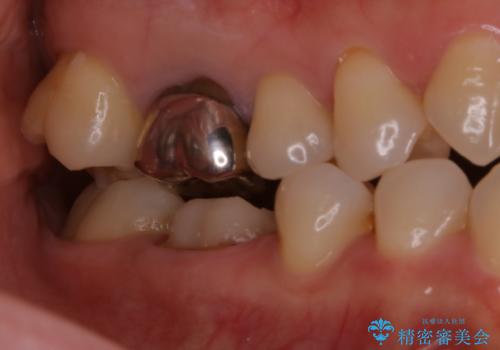

- 歯が欠けてしまったと来院された方です。

メタルインレーが一部欠けており、その下には大きな虫歯ができていました。

再精密根管治療もご提案しましたがご希望されなかったため、今回は土台と被せ物のみ治療介入しました。